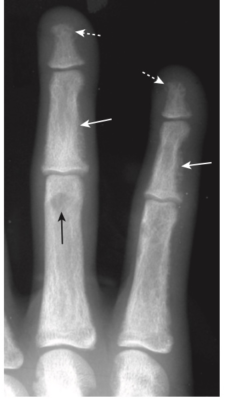

- Tiêu xương dưới màng xương, đặc biệt là ở mặt quay của đốt giữa của ngón trỏ và ngón giữa (Hình -2)